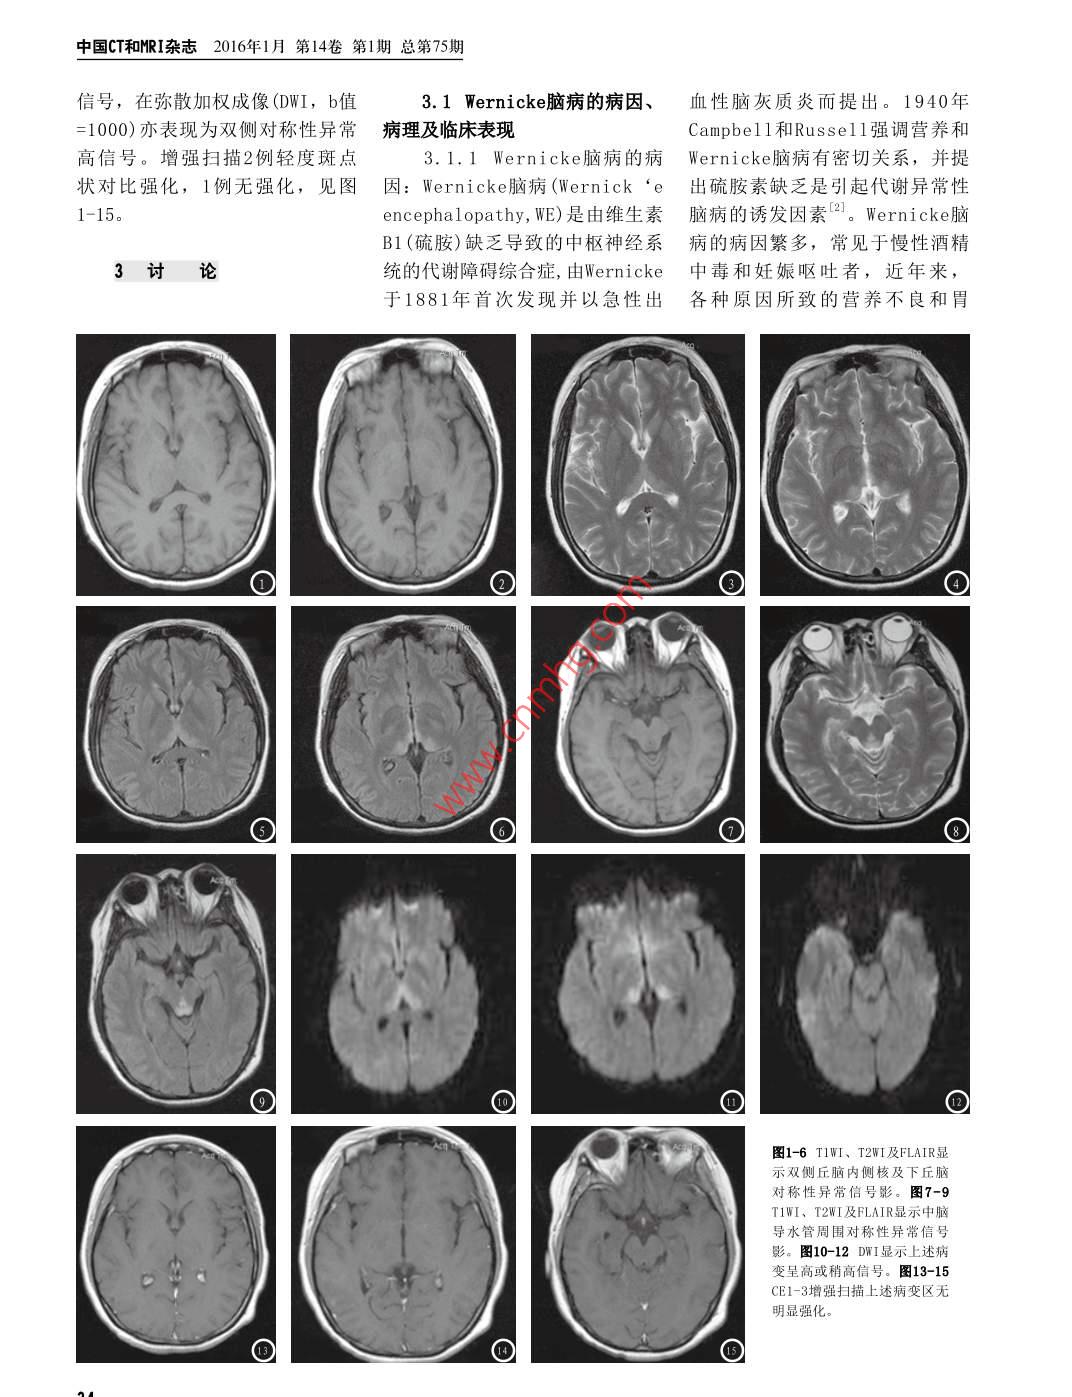

CHINESE JOURNAL OF CT AND MRI, JAN 2016, Vol 14. No I Total No, 75MR Diagnosis of non-alcoholic wernickeEncephalopathppiCAO Hui-fang, LI Hui-ming, LIU Ri-hua, et al., Department of Medical ImagingGeneral Hospital of Police Frontier Defence, Shenzhen 518029, P. R. China論著[Abstract Objective To investigate the value of MRI in the diagnosis of non-alcoholicWernicke encephalopathy. Methods The imaging date of 3 patients with clinically provednon-alcoholic Wernicke encephalopathy were retrospectively analyzed and reviewedcombined with literature. Results 3 patients showed symmetric low signal intensity inTIWI, high signal intensity in T2WI, T2 Flair and DWI in the regions surrounding IIIand IV ventricles, inside of bilateral thalamus, tectum of midbrain and regions surroundingbrain aqueduct. Conclusions Lesion distribution of Wernicke encephylopathy has its非乙醇中毒性characteristics. MRI manifestations of Wernicke encephylopathy have certain specificityand high value in the early diagnosis of this diseaseWernicke腦病的 Mr Key words]wnicke Encephalopathy; Magnetic Resonance Imaging診斷非酒精中毒性 Wernicke腦病是由于維生素B1(硫胺)缺乏所致的嚴(yán)重代謝性腦病,臨床多呈急性或者亞急性起病,眼肌麻痹、共濟(jì)失深圳公安部邊防部隊(duì)總醫(yī)院影像中調(diào)、精神障礙為本病的“三聯(lián)征”,既往臨床診 Wernicke腦病需要心(廣東深圳518029)患者出現(xiàn)典型的“三聯(lián)征”,但是實(shí)際臨床中僅16%的患者會(huì)出現(xiàn)典型曹慧芳李惠明劉日華的“三聯(lián)征”口,所以臨床診斷困難,誤診率高,本研究旨在分析探劉璐討其MRI特征性表現(xiàn),以進(jìn)一步提高對(duì)該病的診斷水平?!菊磕康奶接慚RI在非乙醇中毒性1資料與方法Wernicke腦病診斷中的應(yīng)用價(jià)值。方茁回顧性分析經(jīng)臨床治療確診的3例非乙醇中毒性 Wernicke腦病患者的影像資料1.1一般資料收集我院自2012年3月~2014年2月經(jīng)臨床治療確為1合室旁發(fā)雙側(cè)丘有半診非酒精中毒性Weri腦病3例,男l(wèi)例,女2例,年齡31-52歲,中腦頂蓋區(qū)及中腦導(dǎo)水管周?chē)鷮?duì)稱性異常位年齡41歲,1例急性發(fā)病,由于情緒因素禁食3天后出現(xiàn)眩暈、視幻高信號(hào),T2 Flair成像及彌散加權(quán)成像覺(jué),然后轉(zhuǎn)入昏睡;另外2例均為亞急性起病,病程后期有不同程度的ωW高信號(hào):豬, Wernicke腦病的意識(shí)和精神障礙,臨床表現(xiàn)l例表現(xiàn)為表情淡漠,記憶障礙,四肢共濟(jì)對(duì)其早期診斷具有較高價(jià)值失調(diào),1例表現(xiàn)為四肢軟癱。3例均無(wú)酗酒史【關(guān)鍵詞】 Wernicke腦病;磁共振成像1.2檢查方法使用西門(mén)子 Magneton Symphony1.5T超導(dǎo)MR機(jī)【中圖分類(lèi)號(hào)】R742.8+2選用頭顱線圈,常規(guī)平掃:自旋回波(SE)序列T1WI:TR500ms【文獻(xiàn)標(biāo)識(shí)碼】AD0I:10.3969/j.issn.1672-TE9.4ms;快速自旋回波(FSE)序列T2WI:4200ms,109ms。 Flair序5131.2016.01.011列:TR8340ms,TE9.4ms;增強(qiáng)掃描采用TWSE序列TR500ms9.4ms。平掃和增強(qiáng)掃描均行顱腦橫軸面、矢狀面、冠狀面。對(duì)比劑采用釓噴替酸葡甲胺(Gd-DTPA),按0. 1 mmol/kg,靜脈團(tuán)注法給藥1.3圖像分析由2名高年資放射科醫(yī)生分別對(duì)MRI圖像進(jìn)行分析,分析達(dá)成一致,分析主要重點(diǎn)是病變分布情況及MR特征性表現(xiàn)2結(jié)果通訊作者:曹慧芳3例患者M(jìn)R顱腦平掃均見(jiàn)病灶主要分布于III、IV腦室旁及雙側(cè)丘腦內(nèi)側(cè)、中腦頂蓋區(qū)及中腦導(dǎo)水管周?chē)屹|(zhì)內(nèi),均為雙側(cè)對(duì)稱性分布,雙側(cè)丘腦內(nèi)側(cè)及中腦導(dǎo)水管周?chē)屹|(zhì)內(nèi)最為明顯。T1WI上表現(xiàn)為低信號(hào),T2W上表現(xiàn)為高信號(hào),T2、T2F1air上表現(xiàn)為對(duì)稱性異常高中國(guó)CT和MRI雜志2016年1月第14卷第1期總第75期信號(hào),在彌散加權(quán)成像(DWI,b值3.1 Wernicke腦病的病因、血性腦灰質(zhì)炎而提出。1940年1000)亦表現(xiàn)為雙側(cè)對(duì)稱性異常病理及臨床表現(xiàn)Campbell和 Russell強(qiáng)調(diào)營(yíng)養(yǎng)和高信號(hào)。增強(qiáng)掃描2例輕度斑點(diǎn)3.1.1 Wernicke腦病的病 Wernicke腦病有密切關(guān)系,并提狀對(duì)比強(qiáng)化,1例無(wú)強(qiáng)化,見(jiàn)圖因: Wernicke腦病( Wernick‘e出硫胺素缺乏是引起代謝異常性1-15。encephalopathy,WE)是由維生素腦病的誘發(fā)因素。 Wernicke腦B1(硫胺)缺乏導(dǎo)致的中樞神經(jīng)系病的病因繁多,常見(jiàn)于慢性酒精3討論統(tǒng)的代謝障礙綜合癥,由 Wernicke中毒和妊娠嘔吐者,近年來(lái),于1881年首次發(fā)現(xiàn)并以急性出各種原因所致的營(yíng)養(yǎng)不良和胃圖1-6T1W、T2WI及 FLAIR顯示雙側(cè)丘腦內(nèi)側(cè)核及下丘腦對(duì)稱性異常信號(hào)影。圖7-9TWI、T2WI及 FLAIR顯示中腦導(dǎo)水管周?chē)鷮?duì)稱性異常信號(hào)影。圖10-12DW1顯示上述病變呈高或稍高信號(hào)。圖13-15CE1-3增強(qiáng)掃描上述病變區(qū)無(wú)CHINESE JOURNAL OF CT AND MRI, JAN 2016, Vol 14. No I Total No, 75腸外營(yíng)養(yǎng)導(dǎo)致的非酒精中毒性側(cè)、中腦頂蓋區(qū)、乳頭體、四疊的異常信號(hào)改變更明顯,由于非Wernicke腦病的發(fā)病率明顯提體及中腦導(dǎo)水管周?chē)屹|(zhì),呈嗜酒性 Wernicke腦病患者是首次高,如急性胰腺炎、結(jié)腸癌術(shù)后對(duì)稱性,這些區(qū)域因?yàn)檠趸x發(fā)生硫胺素缺乏代謝性障礙,乳化療后引起間斷惡心、嘔吐病效率高,所以對(duì)硫胺素的缺乏很頭體不會(huì)發(fā)生明顯萎縮,我們的3史,還有報(bào)道AIDS患者和甲亢患敏感。 Wernicke腦病常規(guī)MRI包例病例均未看到乳頭體體積的改者患 Wernicke腦病的風(fēng)險(xiǎn)大大增括TWI、T2WI和T2T2 Flair成變。 Zuccoli c, Santa d等發(fā)現(xiàn)像,以III、IV腦室旁及雙側(cè)丘腦額葉及頂葉等皮質(zhì)區(qū)域受累多見(jiàn)3.1.2 Wernicke腦病的病內(nèi)側(cè)、中腦頂蓋區(qū)、乳頭體、四于非嗜酒性 Wernicke腦病患者,理: Wernicke腦病早期的病理改疊體及中腦導(dǎo)水管周?chē)屹|(zhì)對(duì)稱我們3組病例中均見(jiàn)到皮質(zhì)受損。變?yōu)槭軗p部位神經(jīng)纖維網(wǎng)狀組織性TIWI低信號(hào)、T2WI高信號(hào)、T2MRⅠ擴(kuò)散加權(quán)成像及血管周?chē)>d樣蛻變引起的細(xì) FLAIR成像上明顯的高信號(hào)為特征( diffusion- weighted imaging,胞毒性水腫及血管源性水腫,其性表現(xiàn),軸位T2 Flair像導(dǎo)水管DWI)是常規(guī)MRI的有力補(bǔ)充,它中細(xì)胞毒性水腫占優(yōu)勢(shì)。隨后血周?chē)霈F(xiàn)脫髓樣變化,表現(xiàn)為一使得 Wernicke腦病的MRI陽(yáng)性檢腦屏障被破壞,血管內(nèi)皮細(xì)胞腫種特征性的“n”樣異常改變,但出率大大提高。 Wernicke腦病早脹、外膜變薄、點(diǎn)狀岀血等改該部位病灶的常規(guī)T2WI表現(xiàn)與腦期由于硫胺素缺乏導(dǎo)致細(xì)胞功變,最終導(dǎo)致膠質(zhì)細(xì)胞增生、髓脊液不易分辨,對(duì) Wernicke腦病能障礙而不能維持細(xì)胞內(nèi)外離鞘脫失、神經(jīng)元變性死亡、數(shù)量疑診患者,應(yīng)在常規(guī)軸位TIW和子滲透濃度,進(jìn)而導(dǎo)致細(xì)胞毒減少,常對(duì)稱性累及III、ⅣV腦室T2W基礎(chǔ)上加做冠狀位T2 Flair性水腫,細(xì)胞體積増大,細(xì)胞及中腦導(dǎo)水管、雙側(cè)丘腦內(nèi)側(cè)、掃描,有助于更準(zhǔn)確定位和更敏之間空間減少,水分子彌散障中腦頂蓋區(qū)及中腦導(dǎo)水管周?chē)腋械仫@示病灶。急性期常規(guī)MRI掃礙。而水分子彌散障礙導(dǎo)致表現(xiàn)質(zhì),引起多部位的損害而使臨床描可以于彌散加權(quán)成像(DWI)上呈擴(kuò)散系數(shù)( apparent diffusion表現(xiàn)多樣化,乳頭體是最易受累高信號(hào),由于血腦屏障的破壞, coefficient,ADC)值降低的部位③。注射GD-DTPA后即刻掃描急性期部 Kashihara K等10研究 Wernicke3.1.3 Wernicke腦病的臨床分病灶可明顯強(qiáng)化,急性期増強(qiáng)腦病在急性期DWI信號(hào)増?bào){,彌表現(xiàn): Wernicke腦病臨床表現(xiàn)呈掃描不但可使病變區(qū)明顯強(qiáng)化,散系數(shù)( Apparent diffusion多樣化,多為急性或者亞急性發(fā)還可以增加小病灶檢出率,經(jīng)治 coefficient,ADC)降低顯著,DWI病,眼肌麻痹、共濟(jì)失調(diào)、精神療后復(fù)査強(qiáng)化區(qū)域吸收縮小,甚較T2 Flair更敏感,對(duì) Wernicke障礙為本病的“三聯(lián)征”。在精至消失,這對(duì)于鑒別診斷具有重腦病的早期明確診斷幫助很大,神癥狀方面,可表現(xiàn)為嗜睡、精要意義。非典型MRI表現(xiàn)多見(jiàn)而且動(dòng)態(tài)觀察對(duì)判斷病變的預(yù)后神異常、近記憶減退、計(jì)算力下于前庭神經(jīng)核、腦橋的面神經(jīng)核也很有幫助。ADC值升高的患者給降、反應(yīng)遲鈍、虛構(gòu)等;眼部體和外展神經(jīng)核、中腦的紅核、齒予維生素B1治療后癥狀消失,但征可表現(xiàn)為眼震、兩眼外展及內(nèi)狀核、小腦蚓部、穹窿體、胼胝ADC值正?;蛳陆档牟±齽t遺留收不能、上下運(yùn)動(dòng)不能、同向側(cè)體壓部、尾狀核、額葉及頂葉皮些癥狀視障礙等;共濟(jì)失調(diào)主要表現(xiàn)為質(zhì)的異常信號(hào)影,急性期病灶內(nèi)總結(jié)本組資料并復(fù)習(xí)文獻(xiàn)報(bào)步態(tài)運(yùn)動(dòng)失調(diào)、可伴有言語(yǔ)障可見(jiàn)出血,其病變部位受損嚴(yán)重道,MR是非酒精中毒性 Wernicke礙。表現(xiàn)典型的“三聯(lián)征”患者程度依其累及部位增加而逐漸加腦病首選的影像學(xué)檢査方法,它僅為1/3,所以臨床診斷困難,誤重,當(dāng)病變由乳頭體向下、向上在良好的信號(hào)對(duì)比的基礎(chǔ)上,通診率高。有尸檢研究證實(shí)生前診發(fā)展累及到腦室周?chē)べ|(zhì)及第四過(guò)不通序列和不同方位能全面了斷率僅為20%。所以臨床診斷較腦室底部和頂部皮質(zhì)時(shí),提示病解病變的情況,尤其是DWI為早難,誤診率較高。變已經(jīng)相當(dāng)嚴(yán)重,胼胝體壓部異期診斷提供了新途徑。非酒精中3.2非酒精性 Wernicke腦常在非酒精性 Wernicke腦病中更毒性 Wernicke腦病的分布有特殊病的MR表現(xiàn)MR是非酒精性常見(jiàn)。結(jié)合文獻(xiàn)復(fù)習(xí),我們的3性,MRI表現(xiàn)有特異性,對(duì)其早期Wernicke腦病首選的影像檢査方例患者均未在胼胝體壓部發(fā)現(xiàn)異診斷、治療和改善預(yù)后有較髙價(jià)法,其表現(xiàn)具有特征性,好發(fā)部常信號(hào)。 Lee st等ˉ研究表明在嗜值。位為III、IV腦室旁及雙側(cè)丘腦內(nèi)酒性 Wernicke腦病患者中乳頭體中國(guó)CT和NRI雜志2016年1月第14卷第1期總第75期參考文獻(xiàn)arcuate fasciculus in patients [8] Zuccoli G, Santa d, cruz D, etwth conduction a iaal. MR imaging finding instudy of the Wernicke-56 patients with WernickeMr Baard L, Ulrichsen J, NielsenGeschwind model [J. Neurolencephalopathy: NonWernickes encephalopa thyRes,2010,32(7):775-778a lcoholics may differ fromn patients with alcohol [5]Sakurai K, Sasaki S, Hara M, et, al.alcoholics[J].AJNR Am Ji thdrawl symptoms, Gds krWernicke encephalopa thyLaeger,2010,12(28):2054-2058Neuroradio1, 2009, 30(1):171with cortical a bnaormali[2]Nakatani-Enomoto s, Mor iyties: clinicoradiological [9] Kashihara K, Irisawa M DiffusionA, Kikuchi s, et al. Wernickefeatures: report of 3 new casesweighted magnetic resonanceencephalopathy in a nonand review of literature [J]. eurIic pa t wi himaging in a case of acuteNeurol.2009,62(5):274-280.Wernicke encephalopa thy.diabetic nephropathy under [6]Zuccoli G, Motti L, AtypicalJ Neurol Neurosur gWernicke encephalopathyPsychiatry, 2002, 73(2): 181Shinkeigaku. 2010. 50(6): 409showing lesions in the carnial[10]宮旭海,李雪松,楊鳳民411.nerve nuclei and cerebe l lum. j等. Wernicke腦病致小腦可逆性脫[3]韓順昌,蒲傳強(qiáng),黃旭升,等. Wernicke腦病的臨床、影像學(xué)Neuroma g,2008,18(2):194-197.髓鞘性改變1例[J.中國(guó)CT和MRI雜64-6及病理特點(diǎn)[J].臨床神經(jīng)病學(xué)雜[7] Lee St, Jung YM,NaDL,et志,2006,19(2):167-169a l Corpus callosum a trophy in[4]Zhang Y, Wang C, Zhao X, etWernicke encephalopathy [J]al Diffusion tensor imaging(本文編輯:丁賀宇)J Neuroimaging, 2005, 15(4).367depicting damage to the【收稿日期】2016-12-05(上接第29頁(yè))綜上所述,臨床采用MRI增術(shù),2012,28(10):1797-1800強(qiáng)掃描檢查與CT灌注成像對(duì)腦膜[61重江寧,微小腦展瘤CT與MR1分析[J].安徽醫(yī)學(xué),2010,31(3):266采用MRI增強(qiáng)掃描檢査對(duì)臨床治療瘤臨床分型診斷具有較高應(yīng)用價(jià)269具有重要作用,主要是因患者眼值。同時(shí)采用CT灌注成像可為臨[η]陳建強(qiáng),韓向君,史克珊,等.CT眶內(nèi)腦膜瘤與顱內(nèi)腦膜瘤存在較床提髙較為豐富的血供信息,因血管成像在顱底腦膜瘤手術(shù)中為相似的MRI信號(hào),且大多數(shù)腫此值得進(jìn)一步推廣,以為臨床腦的應(yīng)用[J].中國(guó)醫(yī)學(xué)影像技術(shù),2010,30(4):631-634瘤在TIⅥ上表現(xiàn)為低信號(hào)或等信膜瘤疾病診斷和治療提供重要參[8]郭翠萍,張雪林,呂曉飛,等.鈣號(hào),因此極易鑒別。經(jīng)本次研究考信息化性砂粒體型腦膜瘤的CT與發(fā)現(xiàn),CT灌注成像臨床診斷分型MRI診斷[J].臨床放射學(xué)雜志,2011,30(1):22-25符合率為91.03%(71/78)與MRI增參考文獻(xiàn)[9]許峰,張榮偉,袁紹紀(jì),等,320強(qiáng)掃描檢查比較94.87%(74/78)比層CT灌注成像評(píng)估竇旁腦膜瘤較(x2=1.74,P>0.05)。采用CT[1劉勇,陳正君,羅麗,等.CT與MRI在小瘤周水腫的價(jià)值[J].江蘇醫(yī)藥,2011,37(7):811-813.灌注成像檢査腦膜瘤,其腦血流腦膜瘤診斷中的應(yīng)用價(jià)值[J].中國(guó)CT和MRI雜志,2014,12(1):33-35[10]陳建強(qiáng),韓向君,史克珊,等,CT、量(CBF)和腦血容量(CBV)及平均[2]孟慶梅,張洪業(yè),非典型性腦膜瘤的MRA在老年腦膜瘤手術(shù)切除計(jì)劃通過(guò)時(shí)間(MTT)、血管表明通透CT、MRI表現(xiàn)[J].中國(guó)CT和MRI雜制定中的價(jià)值[J].臨床放射學(xué)雜性(PS)與對(duì)其對(duì)側(cè)腦組織比較(P志,2014,12(4):66-68志,2011,26(12):1742-1745<0.05):且不同類(lèi)型腦膜瘤的【3]葉紅,黃朝南,朱輝嚴(yán),等CT及M11樂(lè)維婕,余強(qiáng)顱外腦膜瘤的T和對(duì)非典型腦膜瘤的診斷價(jià)值[J].中MRI表現(xiàn)[J].中國(guó)醫(yī)學(xué)計(jì)算機(jī)成像CBF和CBV及PS比較(P<0.05)。2CT和MRI雜志,2012,10(1):24雜志,2011,17(6):490-493種檢查方法與臨床病理診斷符合25+45.[12]李慶祝,翟建,韓劍劍,等.64率均在90%以上,具有較為實(shí)用41任峰,高嶺,姚鳳明等,CT聯(lián)合MRI排CT雙期血管造影在腦膜瘤術(shù)對(duì)鈣化性腦膜瘤的臨床診斷療效評(píng)前的臨床應(yīng)用價(jià)值[J].安徽醫(yī)的診斷價(jià)值。同時(shí)在血流信息方價(jià)[J.健康研究,2014,34(3):259學(xué),2014,35(5):630-63面,采用CT灌注成像可為臨床提260+263供更為準(zhǔn)確的信息,這與相關(guān)研5]謝曉潔,鄧亞敏,曾憲春,等,雙本文編輯:汪兵)源CT雙能量顱腦CTA虛擬平掃診究報(bào)道一致斷腦膜瘤[J].中國(guó)醫(yī)學(xué)影像技【收稿日期】2015-12-05